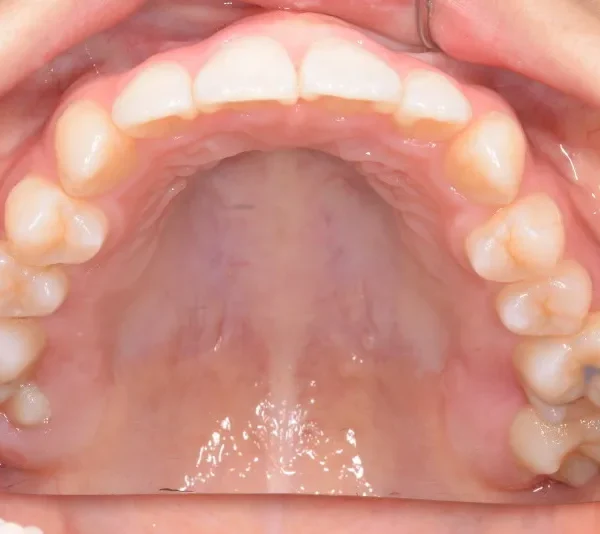

治療終了後

低学年時は取り外しの装置を使用し、高学年になってからは見えにくい固定式の装置を使用して治療しました。

治療回数48回、7年2ヶ月の治療期間で矯正治療を終了しました。

主訴が改善され、ご満足頂きました。